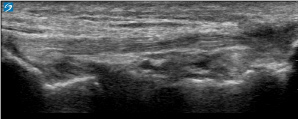

Knee Lateral Collateral Ligament (LCL) Inflammation Image